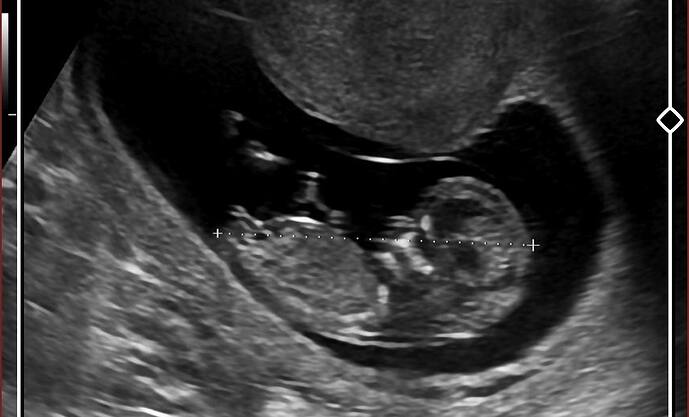

Kese yuvarlak dengesiz şekilli dedi

Yuvarlak değil dedi

Benim ilk vajinal bakıldıgında 4 haftalıktı kese yusyuvarlaktı sonra Hilal şekli oldu 9 haftalıkken.12 haftada da tekrar yuvarlak oldu sureklı degısıyor kese.su an 18 haftalık iki doktor da erkek dedi ama ayrıntılıya girmeyene kadar guvenmıyorum

Benim kızlarım da kese fasulye gibi uzundu bunda yuvarlaktı genelde

Vajinal bakıldığında 4 haftalık ultrasonda yuvarlaktı sizinkine benziyordu

Tahmin etmesi zor bi keseye benziyor ya

ama kız gibime geldi sağlıkla gelsin inşallah çok küçük gorunuyo ayrıca belki ondan pek bilemedim ama kız gibi ![]()

Bence erkek Tuğba

Kestiremedim ama bence kız

Bende emin olamıyorum bir kız diyolar bir erkek